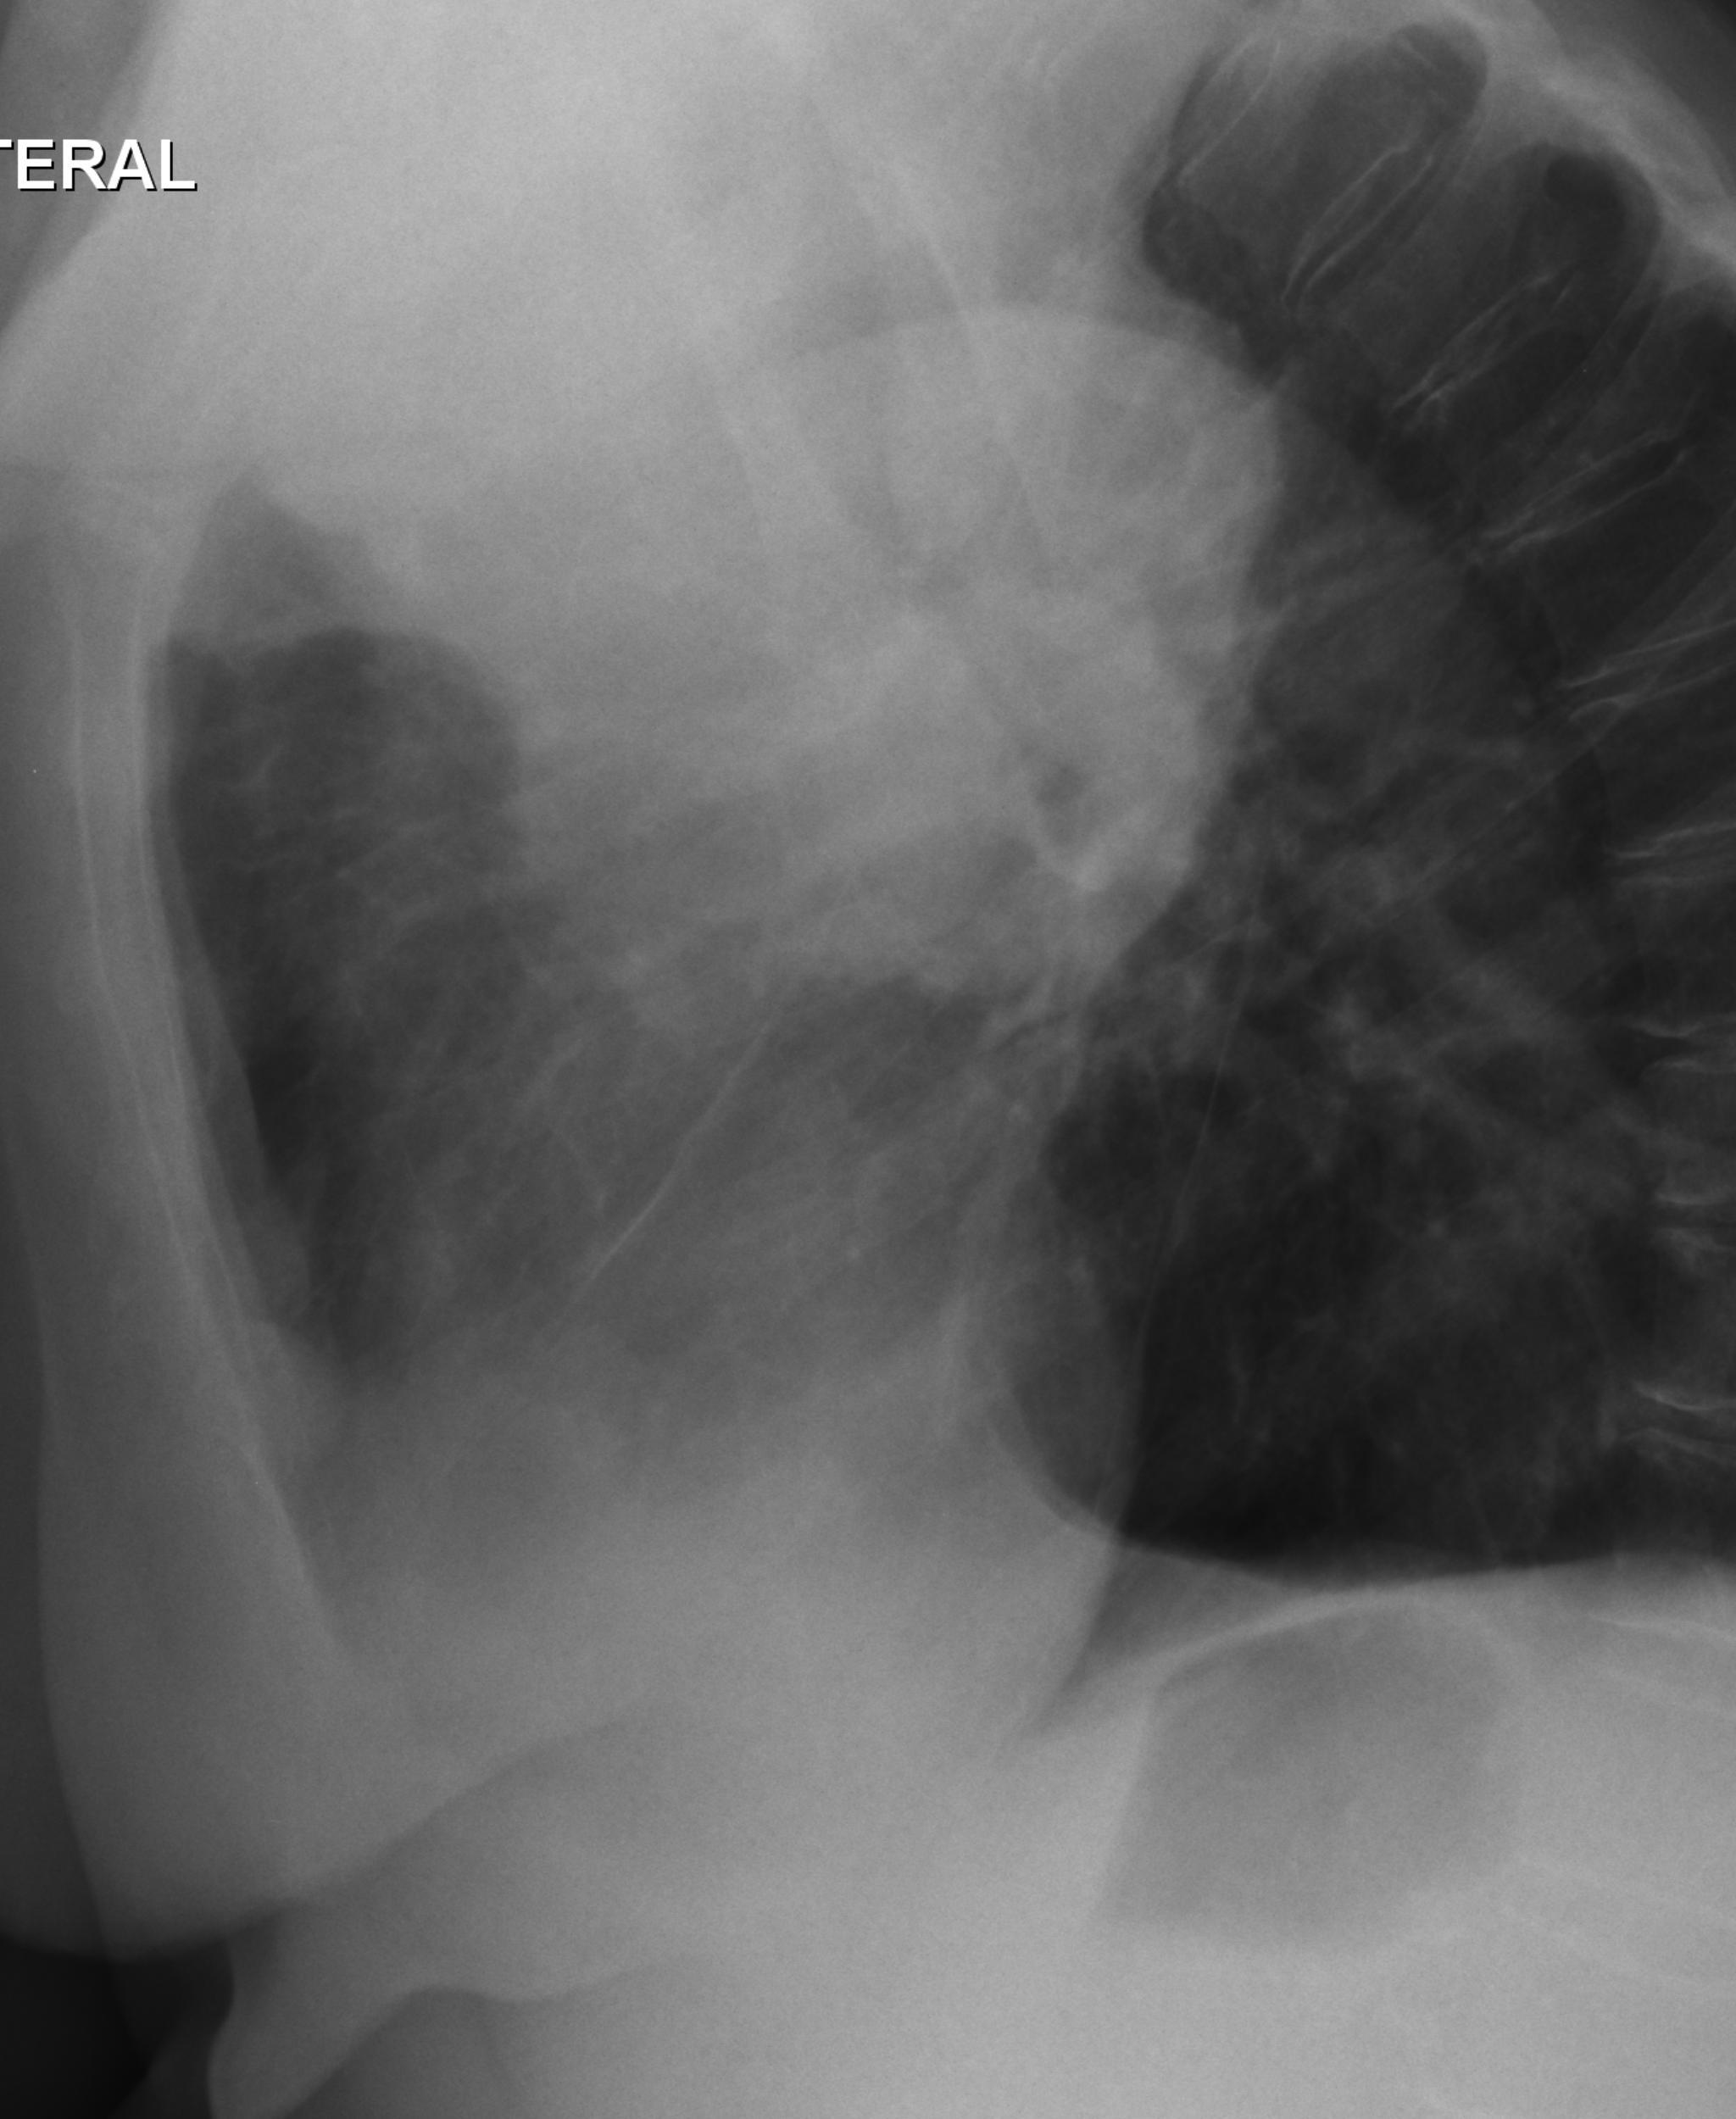

Caso relatado na Reunião de Discussão de Casos Clínicos do Hospital Universitário Prof. Polydoro Ernani de São Thiago, iniciada pelos Profs. Jorge Dias de Matos, Marisa Helena César Coral e Rosemeri Maurici da Silva, em julho de 2017. No dia 14 de junho de 2018, no auditório do HUPEST, realizou-se a apresentação e discussão do caso cujo registro é apresentado a seguir. Trata-se da discussão de onze casos em radiologia torácia, de forma interativa com a plateia, e assim ocorre também neste artigo.